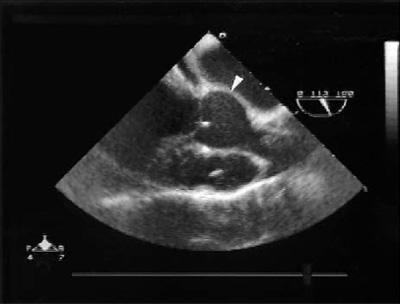

An intraoperative TEE (Fig. 1) confirmed the presence of a nonruptured ASV. A transverse aortotomy was made 5 mm above the sinotubular junction (STJ), in healthy tissue above the lesion. The STJ was sized at 25 mm, and the aortic annulus was estimated at 27 mm. A 27-mm Freestyle® aortic root bioprosthesis (Medtronic, Inc.) was selected. The ASV was measured, and its perimeter was smaller than the height and width of the porcine aortic wall adjacent to the noncoronary cusp. The bioprosthesis was then rotated 120 degrees in order to position its right sinus over the patient's affected noncoronary sinus. This maneuver enabled us to completely cover the ASV with the bioprosthesis. Interrupted 4-0 braided polyester inflow sutures were placed on a plane parallel to and below the aortic annulus. The valve was seated and trimmed (Fig. 2). The ASV was then completely excluded with the continuous outflow suture line. Before we declamped the aorta, warm cardioplegic solution was infused, followed by warm blood. Blood infusion was continued via the coronary sinus until strong cardiac contractions were present and air bubbles were no longer visible in the TEE. The remainder of the operation was completed in the usual manner. Intraoperative TEE, with volume and pressure loading, demonstrated complete exclusion of the ASV (Fig. 3).

Fig. 1 Intraoperative transesophageal echocardiogram shows the nonruptured aneurysm of the sinus of Valsalva (arrowhead).